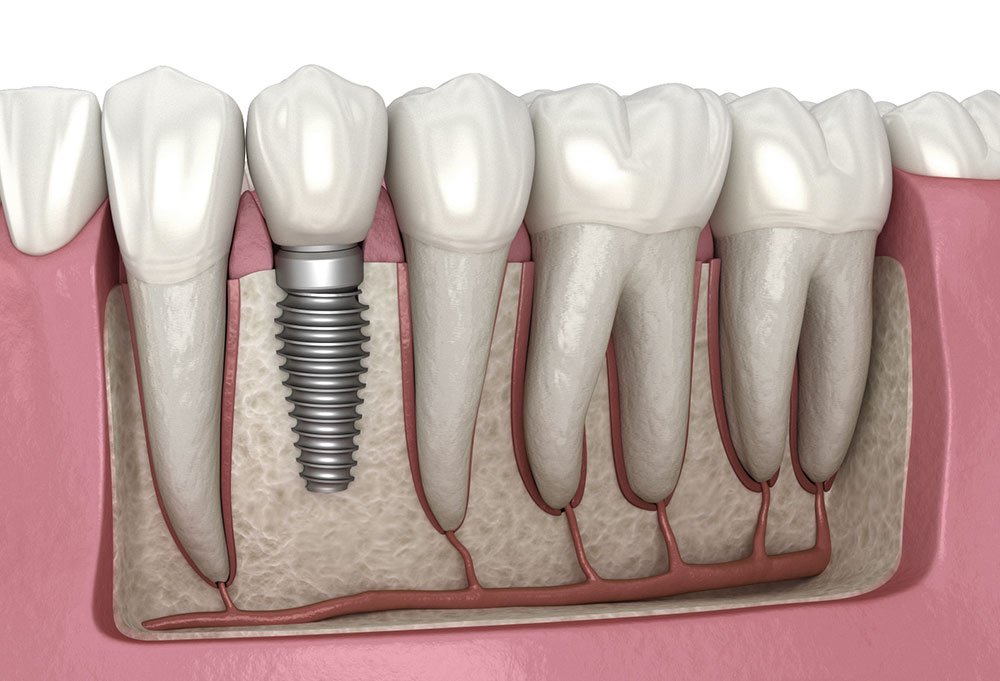

Dental Implants

Dental Implants

Dental implants provide a permanent and natural looking solution for missing teeth by replacing both the tooth root and visible crown. At Dr. Ingale Dental Clinic, advanced implant planning, digital imaging, and precise surgical techniques ensure safe placement and long-term stability for patients across Pimpri Chinchwad and Pune. Implants restore chewing strength, preserve jawbone health, prevent shifting of nearby teeth, and improve speech clarity while delivering confident, natural smile aesthetics for everyday comfort and function.

Each implant treatment is customized based on bone condition, medical history, and functional needs to achieve predictable healing and durable results. Our dental team provides detailed consultation, hygiene guidance, and regular follow-up care near PCMC Metro Station to maintain implant success. With proper maintenance and professional monitoring, dental implants can last many years, offering reliable tooth replacement, improved confidence, and strong oral health support for long-term wellbeing.